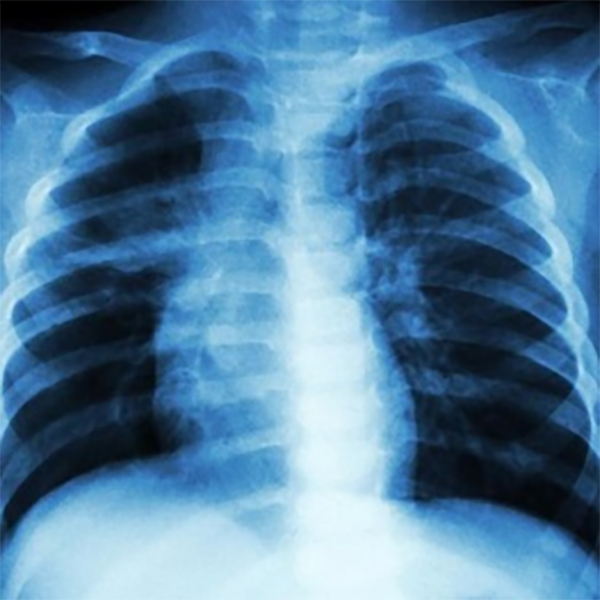

Tuberculosis (TB) testing typically utilizes a variety of methods to determine if an individual has been infected with Mycobacterium tuberculosis. The Mantoux tuberculin skin test (TST) is the most common diagnostic test, involving the injection of a small amount of purified protein derivative (PPD) into the forearm skin. A positive reaction, characterized by a raised, red bump at the injection site within 48-72 hours, indicates TB infection. Another approach is the interferon-gamma release assay (IGRA), a blood test that identifies the release of specific proteins (interferon-gamma) by immune cells in response to TB antigens. Chest X-rays may be conducted to identify lung abnormalities like nodules or cavities, which could suggest active TB disease. Sputum tests, where samples are collected and examined for TB bacteria under a microscope or through culture, are also carried out to confirm TB diagnosis and assess drug sensitivity. Additional tests, such as nucleic acid amplification tests (NAATs) and molecular tests, may be employed to detect TB bacteria or drug-resistant strains.